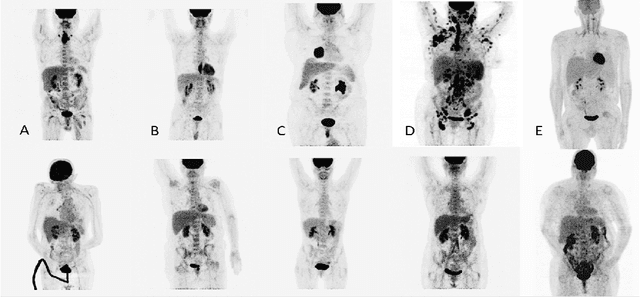

Abstract:One of the most challenges in medical imaging is the lack of data. It is proven that classical data augmentation methods are useful but still limited due to the huge variation in images. Using generative adversarial networks (GAN) is a promising way to address this problem, however, it is challenging to train one model to generate different classes of lesions. In this paper, we propose a deep convolutional conditional generative adversarial network to generate MIP positron emission tomography image (PET) which is a 2D image that represents a 3D volume for fast interpretation, according to different lesions or non lesion (normal). The advantage of our proposed method consists of one model that is capable of generating different classes of lesions trained on a small sample size for each class of lesion, and showing a very promising results. In addition, we show that a walk through a latent space can be used as a tool to evaluate the images generated.